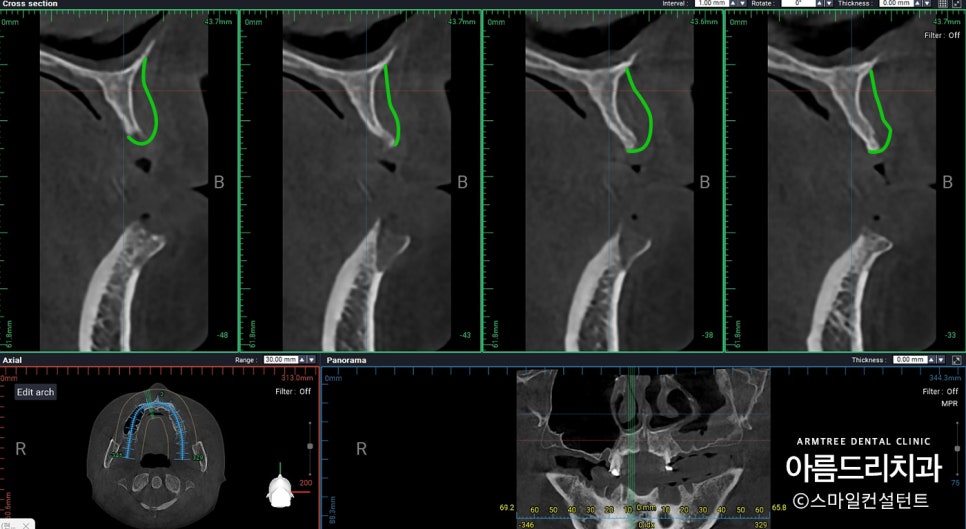

아래 보이는 사진 중 흰색이 뼈입니다.

원래는 녹색라인 정도로 뼈가 있어야 하지만

발치를 한 상태로 오래 지내면 뼈가 흡수되면서

남은 뼈가 사진에서 보이듯 저렇게 얇아집니다.

이렇게 얇은 뼈에 임플란트를

식립하는 것은 쉽지 않은 일이죠.

단순히 심는 것에만 포커스를 둘게 아니라

장기적인 유지와 관리까지 고려를 하는데 아무리

좋은 뼈를 이식해도 내 뼈만큼 좋지는 않습니다.

게다가 환자분이 젊으시기 때문에

오랜 시간 문제없이 사용할 수 있도록

치료하는 것이 중요하다고 판단했습니다.